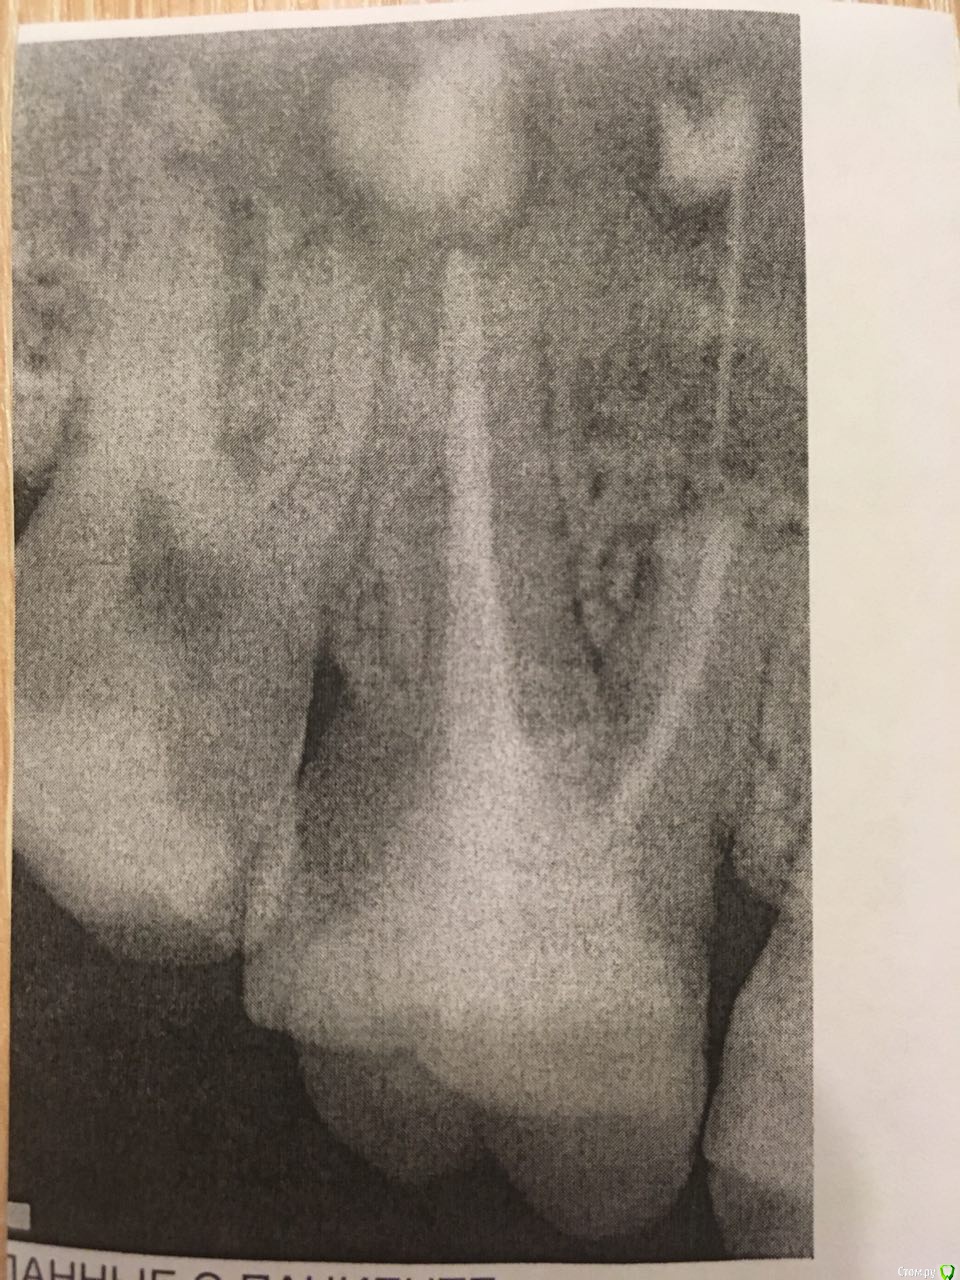

Жалоба на опухоль и боль в левой щеке и  пульсирующую боль в зубе. Сделала снимок в стоматологии рядом с домом, врач подробностей сказать не смогла, кроме того что нужно зуб вырвать и чистить, и посоветовала обратиться в челюстно-лицевую хирургию.

Зуб пломбировался более 8-ми лет назад.

В зубе присутствует хроническое воспаление, которое по каким то причинам сейчас обострилось и есть пломбировочный материал за пределами корня.

В такой ситуации удаление самый прогнозируемый вариант.